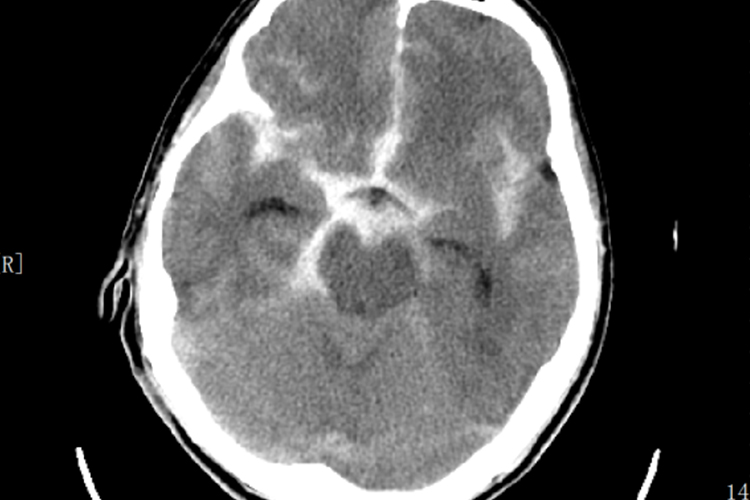

CT表现

蛛网膜下腔出血后48小时内,非强化高分辨率CT可发现≥95%的蛛网膜下腔出血。第一周内CT显示最清晰,显示脑沟与脑池密度增高。

颈内动脉瘤破裂出血以环池最多,大脑中动脉瘤破裂血液积聚病侧外侧裂,大脑前动脉瘤出血集中在前纵裂池。基底动脉瘤破裂后,血液主要聚积于脚间池与环池附近。